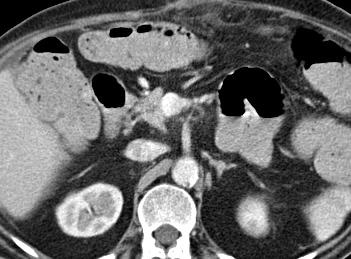

术后第三天增强CT

动脉瘤仍然充盈,但密度减低,所有血管开放